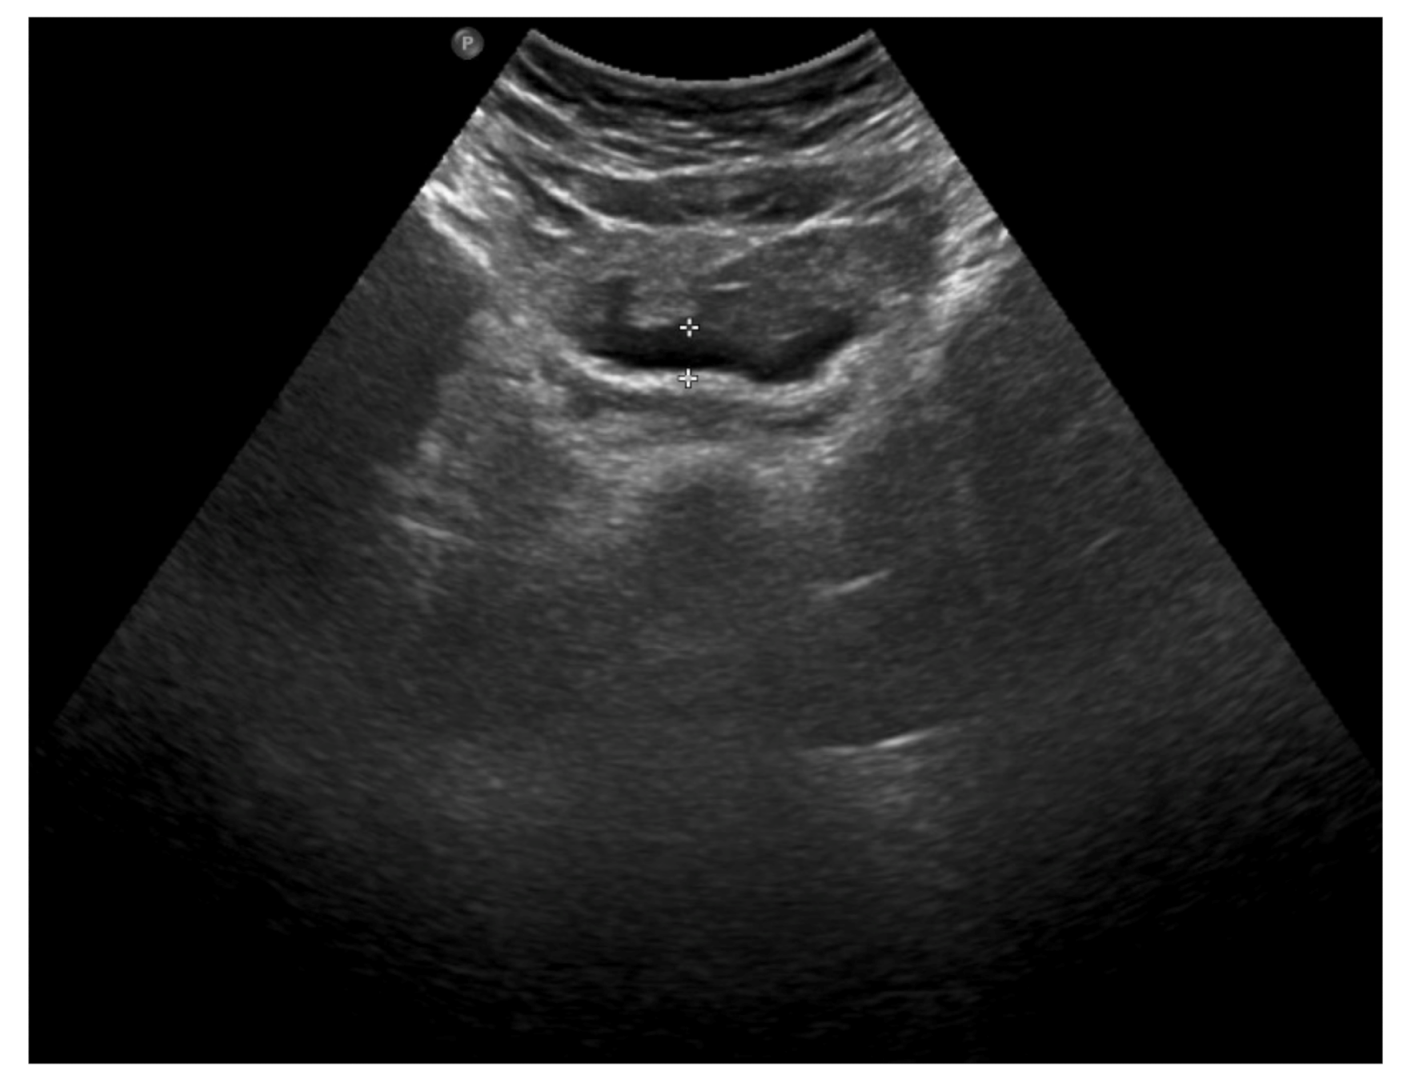

The clinical picture, along with laboratory and imaging investigations, led to the diagnosis of omental infarction. Conservative treatment was introduced. Enema was performed with a good effect. Antibiotic therapy (cefuroxime), analgesic treatment and fluid therapy were implemented. During hospitalization, the subsidence of clinical symptoms and a decline of the inflammatory parameters were observed. In the control abdominal ultrasound, performed on the seventh day of hospitalization, a partial regression of lesions was noted (Figure 4).

Figure 4. The abdominal ultrasound on the seventh day of treatment: partial regression of fluid collections and hyperechoic adipose tissue lesions.